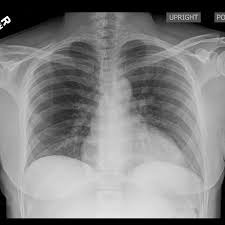

Artificial intelligence in healthcare requires models that are accurate and interpretable. We advance mechanistic interpretability in medical vision by applying Medical Sparse Autoencoders (MedSAEs) to the latent space of MedCLIP, a vision-language model trained on chest radiographs and reports. To quantify interpretability, we propose an evaluation framework that combines correlation metrics, entropy analyzes, and automated neuron naming via the MedGEMMA foundation model. Experiments on the CheXpert dataset show that MedSAE neurons achieve higher monosemanticity and interpretability than raw MedCLIP features. Our findings bridge high-performing medical AI and transparency, offering a scalable step toward clinically reliable representations.